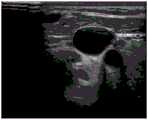

FIG. 3 is an image of a pre-transfusion jugular vein taken in accordance with one embodiment of the present invention.

FIG. 4 is a post-transfusion jugular vein image taken in accordance with one embodiment of the present invention.